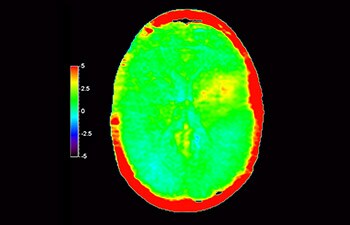

In una società in cui i disturbi neurologici rappresentano un grave problema, Philips si impegna a fornire una efficacia diagnostica senza pari e una guida per il trattamento di tutti i pazienti. Oggi, sebbene la risonanza magnetica sia lo standard di riferimento per l'imaging neuro-oncologico, è comunque possibile migliorarne la precisione nella definizione del grado del tumore e nelle valutazioni di follow-up della terapia. 3D APT (Amide Proton Transfer) è un esclusivo metodo di imaging RM del cervello senza contrasto che permette di ottenere diagnosi più affidabili nel campo della neuro-oncologia. Si avvale della presenza di proteine cellulari endogene per produrre un segnale RM direttamente correlato alla proliferazione delle cellule, un marker dell'attività tumorale. 3D APT è un valido supporto per il personale medico specializzato nella distinzione dei gliomi di grado basso e alto, e nella differenziazione della progressione del tumore rispetto agli effetti della terapia1.